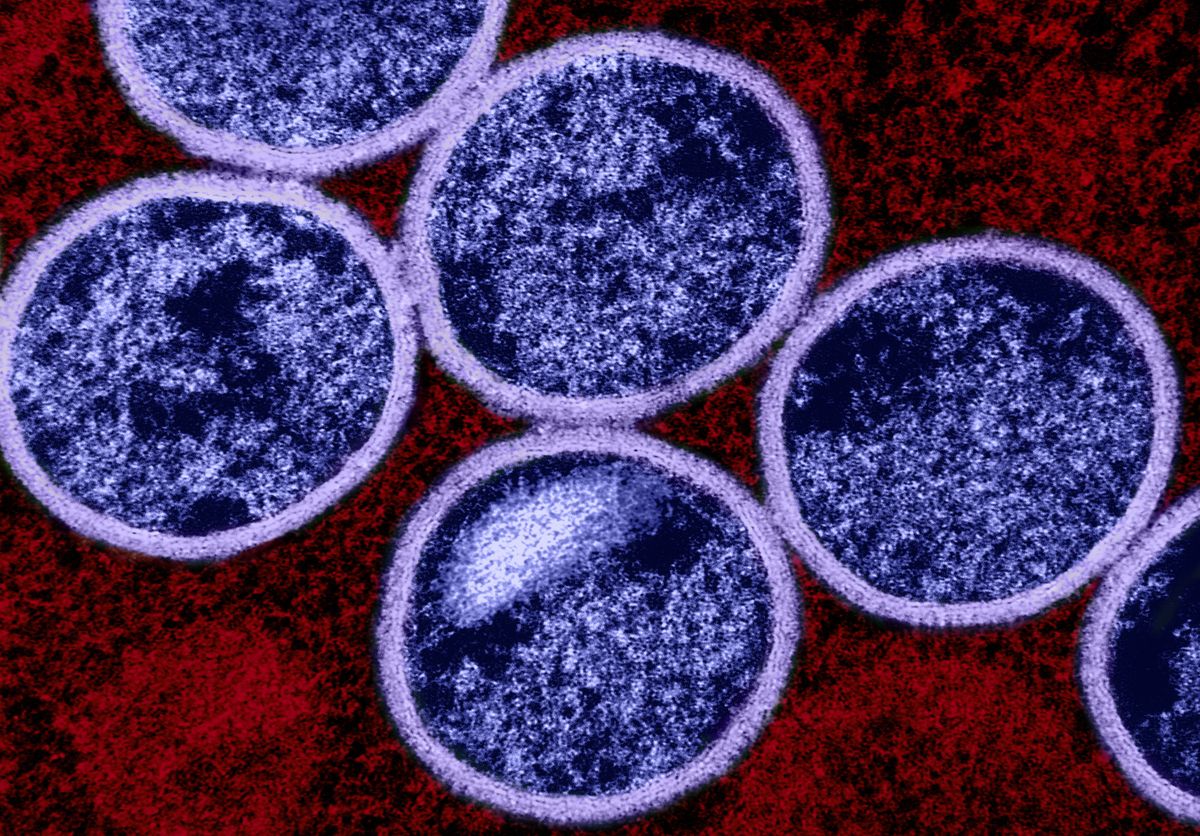

The brain has its own waste disposal system – known as the glymphatic system – that’s thought to be more active when we sleep.

But disrupted sleep might hinder this waste disposal system and slow the clearance of waste products or toxins from the brain. And researchers are proposing a build-up of these toxins due to lost sleep could increase someone’s risk of dementia.

There is still some debate about how this glymphatic system works in humans, with most research so far in mice.

But it raises the possibility that better sleep might boost clearance of these toxins from the human brain and so reduce the risk of dementia.

Here’s what we know so far about this emerging area of research.

All cells in the body create waste. Outside the brain, the lymphatic system carries this waste from the spaces between cells to the blood via a network of lymphatic vessels.

But the brain has no lymphatic vessels. And until about 12 years ago, how the brain clears its waste was a mystery. That’s when scientists discovered the “glymphatic system” and described how it “flushes out” brain toxins.

Let’s start with cerebrospinal fluid, the fluid that surrounds the brain and spinal cord. This fluid flows in the areas surrounding the brain’s blood vessels. It then enters the spaces between the brain cells, collecting waste, then carries it out of the brain via large draining veins.

Scientists then showed in mice that this glymphatic system was most active – with increased flushing of waste products – during sleep.

One such waste product is amyloid beta (Aβ) protein. Aβ that accumulates in the brain can form clumps called plaques. These, along with tangles of tau protein found in neurons (brain cells), are a hallmark of Alzheimer’s disease, the most common type of dementia.

In humans and mice, studies have shown that levels of Aβ detected in the cerebrospinal fluid increase when awake and then rapidly fall during sleep.

But more recently, another study (in mice) showed pretty much the opposite – suggesting the glymphatic system is more active in the daytime. Researchers are debating what might explain the findings.

So we still have some way to go before we can say exactly how the glymphatic system works – in mice or humans – to clear the brain of toxins that might otherwise increase the risk of dementia.